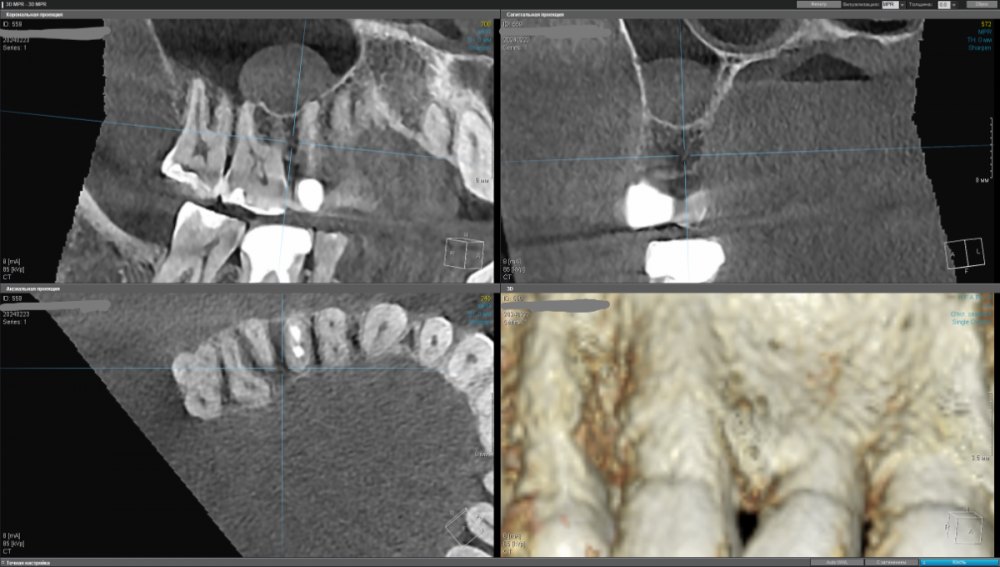

kamacho Опубликовано 15 февраля, 2024 Поделиться Опубликовано 15 февраля, 2024 Уважаемые специалисты. Беспокоит 15 зуб Коронка стоит 2-4 года. Беспокоит переодическая кровь при чистке флосом и иногда неприятный запах между 16 и 15 зубом (как правило ближе к 15ому) Иногда теряю обоняние. Обильный серый налет на языке по утрам. После ирригатора, флоса и тщательной чистки обоняние возращается. В клинике сказали что коронка прилегает хорошо и выступов нету(посещал дважды). Если будет возможность дополню тему прицельными снимками. 1)Скажите пожалуйста, есть ли показания для лечения этого зубика? 2)Могут ли не до конца пролеченные корни вызывать такую симптоматику ? 3)И если да то что лучше сделать? Стоит ли заменить на имплант ? Так же буду очень признателен если кто-то предложит специалиста Москве к которому можно было бы обратиться. Немножко предыстории и описание кт если вам интересно. Корни пломбировали где-то лет 10-15 назад. Сначала закрывали пломбой, которая потемнела. Обратился по поводу эстетики в клинику, терапевт хотела перелечить каналы, но когда сняла пломбу увидела цемент и сказала что не получится. Предложили закрыть коронкой и не трогать. С тех пор обращатся в клиннику дважды с жалобами про кровь и трудность гегиены. Предлагали акуратней пользоватся нитью и чаще следить за гегиеной. 1.5 зуб — депульпирован. Коронковая часть: восстановлена искусственной коронкой. Вариант строения: два корня, два канала. Обтурация: ЩК - установлен штифт на 1⁄2 длины корня, далее канал обтурирован пломбировочным материалом, не доходя до верхушки корня на 2,4 мм. НК - установлен штифт на 1⁄2 длины корня, далее канал обтурирован пломбировочным материалом, не доходя до верхушки корня на 2,9 мм. Периодонтальное пространство: не изменено. Пародонт: без особенностей. Ссылка на комментарий

kamacho Опубликовано 24 февраля, 2024 Автор Поделиться Опубликовано 24 февраля, 2024 Попробую привлечь ваше внимание дополнительными снимками. Вопросы которые я себе задаю когда смотрю на КТ: 1) Между 14 и 15 зубом, это убыль фуркации или артефакт при съемке кт ? 2) В районе 37 ого зуба это артефакт или кариес ? Я пытаюсь санировать ротовую полость уже наверное лет пять, и никогда не удается решить проблему. Прошел множество клинник (наверное штук 5-6, включая 1 зарубежную). Но после попыток лечения, возникает одна и таже проблема, как только начинаю добавлять углеводы(не сладости) в рацион, какой-то очаг инфекции дает о себе знать. Буду очень признателен если поможете советом или догадкой. Ссылка на комментарий

kamacho Опубликовано 24 февраля, 2024 Автор Поделиться Опубликовано 24 февраля, 2024 (изменено) Так же приложу документ-опись риентгенолога по всем зубками с изображениями. снимок был сделан в 22 году. Наврятли кто-либо захочет перечитывать такое количество информации ради развлечения. Но для истории добавлю. Изменено 24 февраля, 2024 пользователем kamacho Ссылка на комментарий

Carioznik Опубликовано 25 февраля, 2024 Поделиться Опубликовано 25 февраля, 2024 15.02.2024 в 18:43, kamacho сказал: есть ли показания для лечения этого зубика? По идее есть, но нужно разбираться 15.02.2024 в 18:43, kamacho сказал: Могут ли не до конца пролеченные корни вызывать такую симптоматику ? Нет 17 часов назад, kamacho сказал: Между 14 и 15 зубом, это убыль фуркации Нет. Похоже, что на 14 есть кариес. Возможно это и причина кровоточивости и запаха. Но нужно смотреть настоящую КТ , а не скрины. 18 часов назад, kamacho сказал: районе 37 ого зуба это артефакт или кариес ? Больше на артефакт похоже, но это не точно: нужно смотреть настоящую КТ , а не скрины 1 Ссылка на комментарий